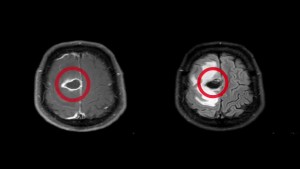

14 MAR 2016 PNI neurosurgeon, Dr. Garni Barkhoudarian gives a patient good news, “You have tapeworms!” PNI Press Releases and News Clips Share: Previous Dr. Santosh Kesari improves teen’s health with game-changing approach Next New formula can predict professional football players’ long-term concussion damages